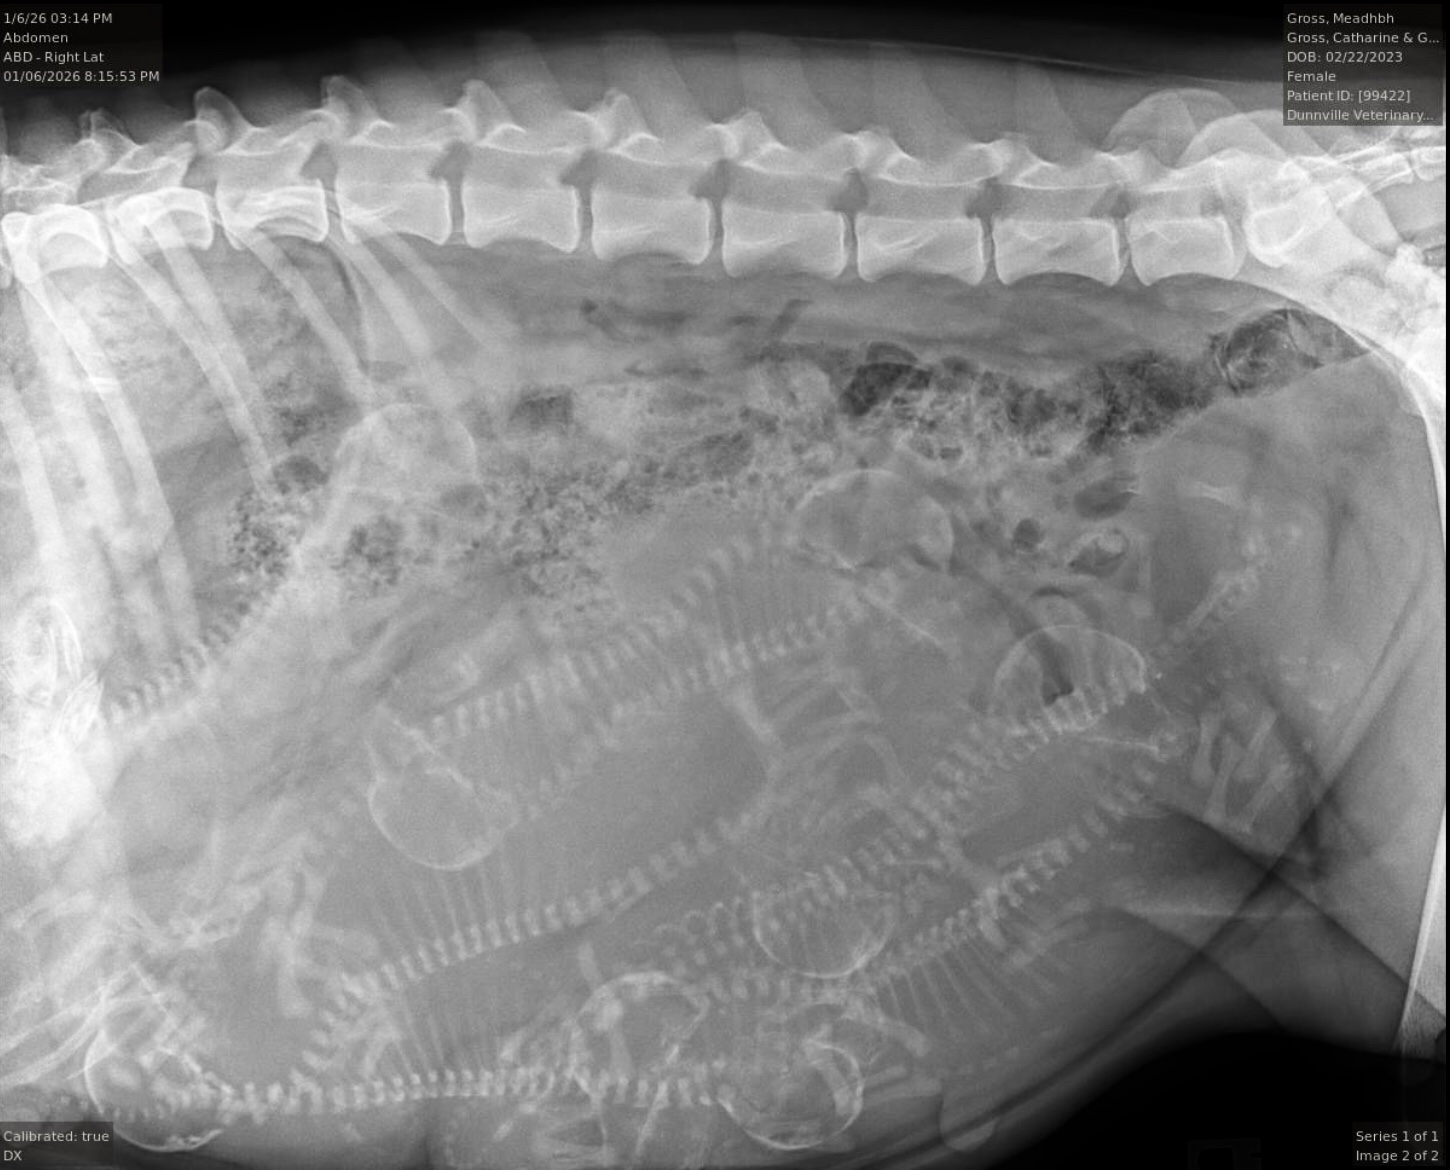

Our Meadhbh “Ch Braefield Shutterfly” has been mated to Gunner “Ch Goldnote’s There Is Only One” the pregnancy has been confirmed and Pups are due around January 11th. They will be able to go to their new homes around the third week of March 2026 This will be Meadhbh’s first litter

Can you guess how many puppies there are???